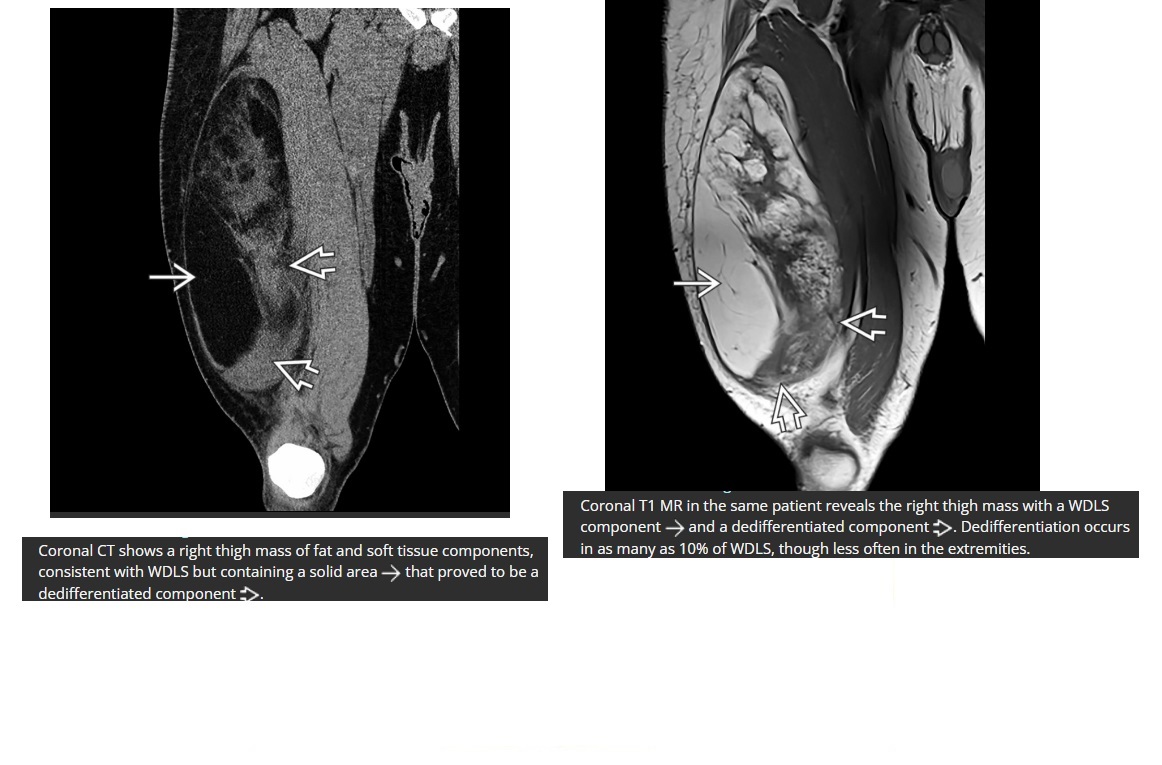

Osteochondroma

points away from the joint

Pedunculated lesion arising from surface of bone with continuity of normal cortex and marrow

Metaphysis/metaphyseal equivalents (rarely diaphysis)

Multiple =

Diaphyseal aclasia/Multiple Hereditary Exostoses - Metaphysis region of tubular bones of extremities

Cap > 1.5cm ??? chondrosarcomatous transformation

ng. avian spur points towards the joint